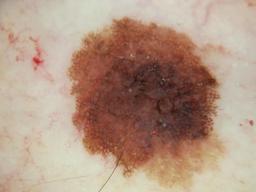

{

"age_approx": 55,

"anatom_site_general": "head/neck",

"clin_size_long_diam_mm": "9.00",

"concomitant_biopsy": true,

"diagnosis_1": "Malignant",

"diagnosis_2": "Malignant melanocytic proliferations (Melanoma)",

"diagnosis_3": "Melanoma in situ",

"diagnosis_4": "Melanoma in situ, Lentigo maligna type",

"diagnosis_confirm_type": "histopathology",

"family_hx_mm": false,

"image_type": "dermoscopic",

"personal_hx_mm": false,

"sex": "male"

}